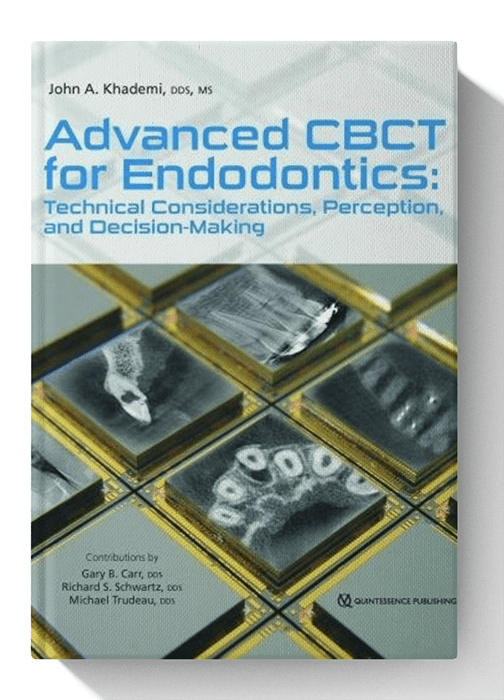

Advanced CBCT for Endodontics: Technical Considerations, Perception, and Decision-Making 1st Edition

Regular price $29.99 USDRegular priceUnit price / per -